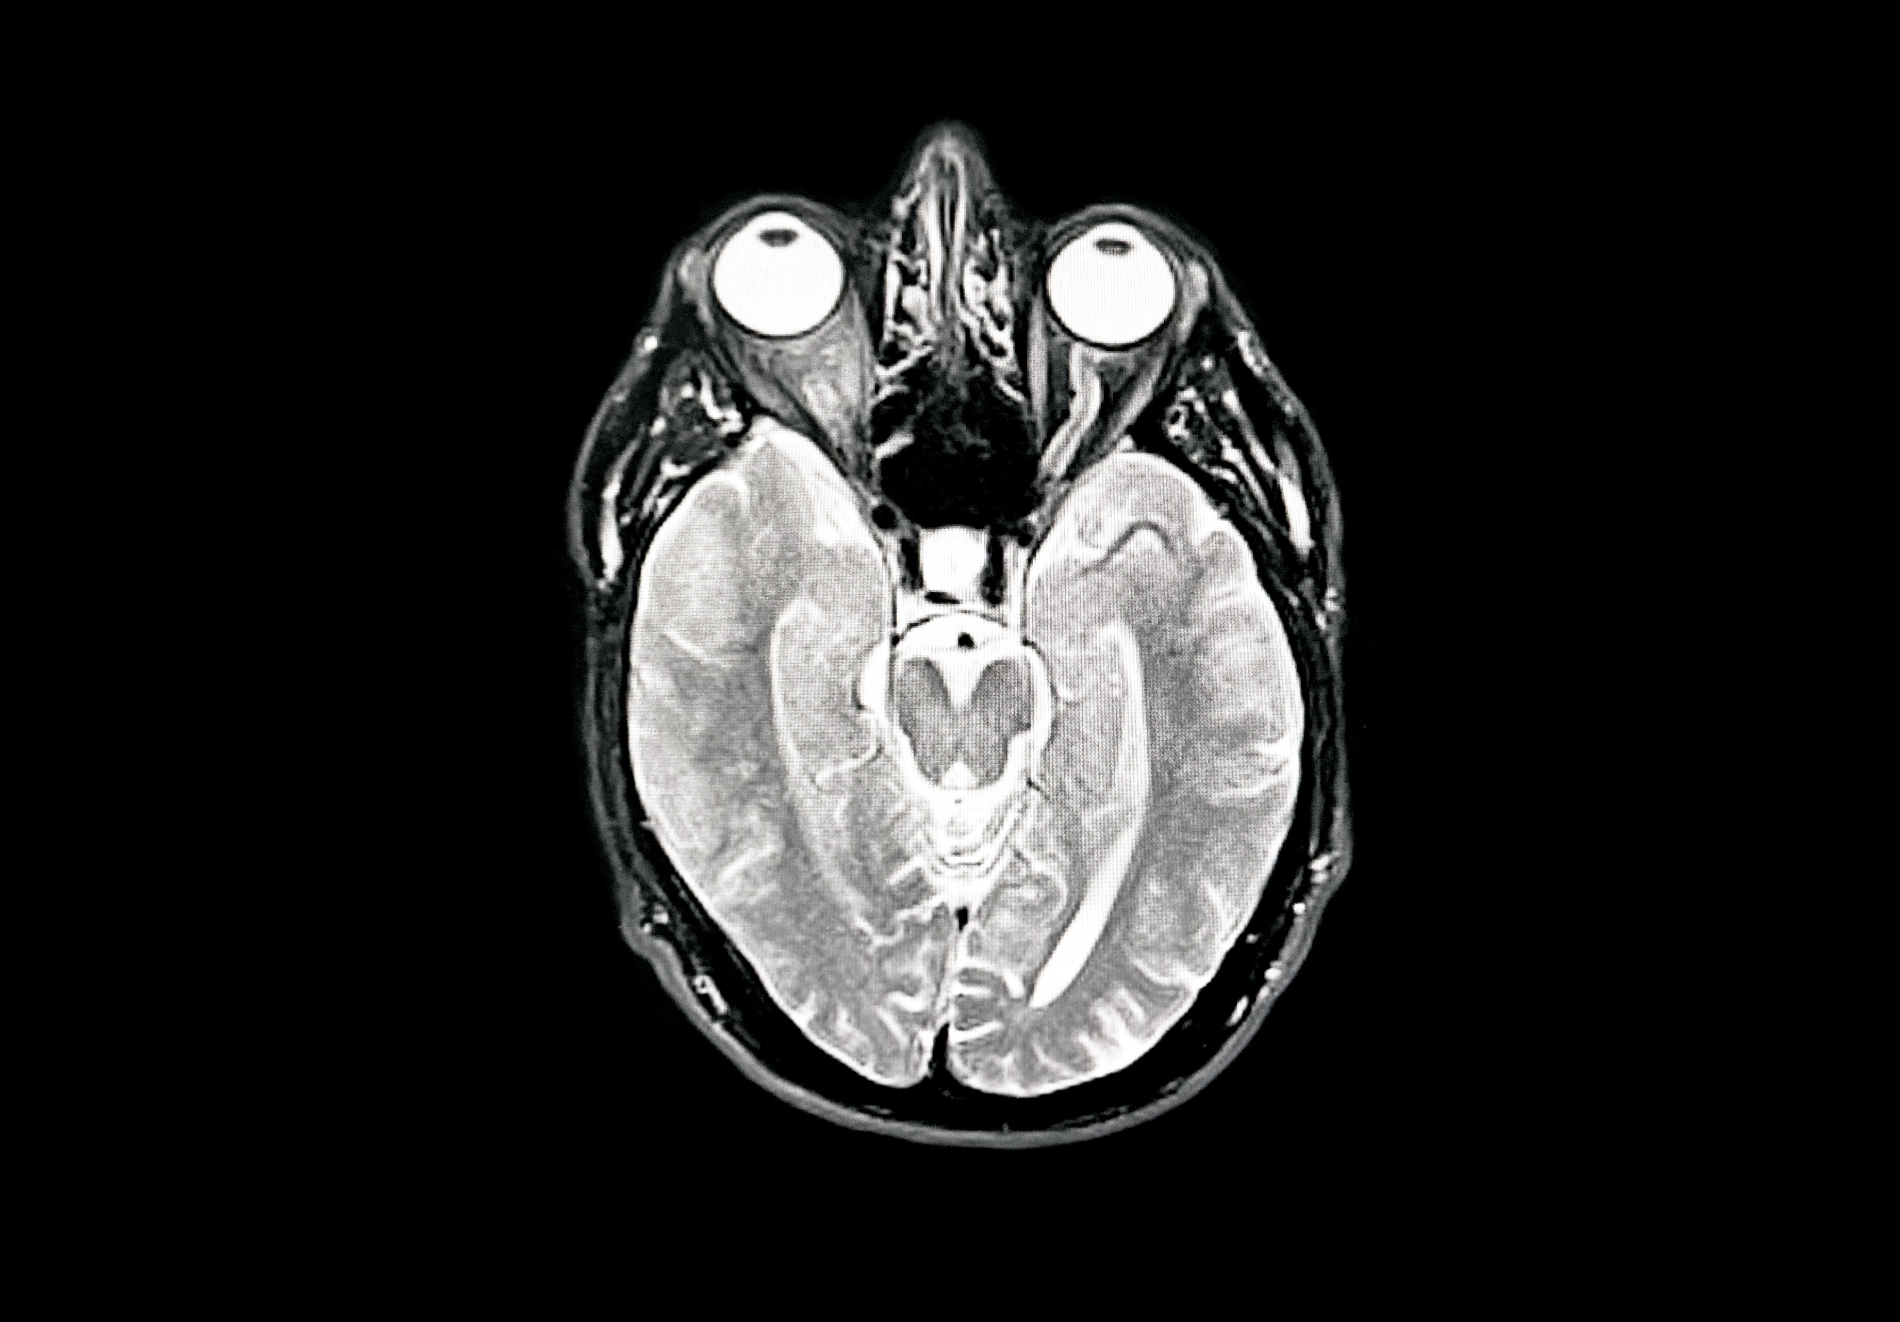

ورغم التقدم في دراسة الزهايمر، لا يزال تشخيصه يمثل تحديا حقيقيا في الطب الحديث. فحتى اليوم يعتمد الأطباء على مجموعة من الاختبارات المعرفية، والتاريخ الطبي للمريض، إضافة إلى تقنيات التصوير الدماغي للكشف عن اللويحات والتشابكات. لكن، وبعد أكثر من مئة عام من اكتشاف المرض، لا يزال الأطباء والباحثون غير متفقين بشكل كامل على الطريقة الأكثر دقة وحسما لتشخيص الزهايمر، مما يعكس تعقيد هذا المرض وطبيعته المتشابكة.

يتمحور الخلاف حول سؤال أساس، فهل يعد الزهايمر مرضا بيولوجيا يمكن تعريفه من خلال وجود بروتينات معينة في الدماغ، أم أنه حالة سريرية لا يمكن تشخيصها إلا عندما تظهر أعراض إدراكية واضحة إلى جانب المؤشرات الحيوية؟

يرى بعض العلماء أن وجود التغيرات البيولوجية في الدماغ، مثل تراكم بروتين الأميلويد، قد يكون كافيا لاعتبار الشخص مصابا بالمرض حتى قبل ظهور الأعراض. ويركز هذا التوجه على التغيرات التي تحدث داخل الدماغ في المراحل المبكرة جدا من المرض، والتي قد تسبق ظهور المشكلات في الذاكرة والتفكير بسنوات عديدة.

وتنص معايير جمعية الزهايمر لعام 2024 على أن وجود بروتين الأميلويد في الدماغ يعد مؤشرا رئيسا الى المرض. ومع ذلك، تؤكد هذه المعايير في الوقت نفسه أن إجراء الفحوص أو بدء العلاج ينبغي أن يكون مرتبطا بوجود أعراض إدراكية لدى المريض، وليس اعتمادا على المؤشرات البيولوجية وحدها.

فيما يطرح فريق عمل دولي من الباحثين رؤية أكثر تحفظا، إذ يشترط لتشخيص الزهايمر توافر ثلاثة عناصر معا، وجود بروتين الأميلويد، ووجود بروتين تاو المرتبط بتلف الخلايا العصبية، إضافة إلى ظهور أعراض إدراكية واضحة لدى المريض.